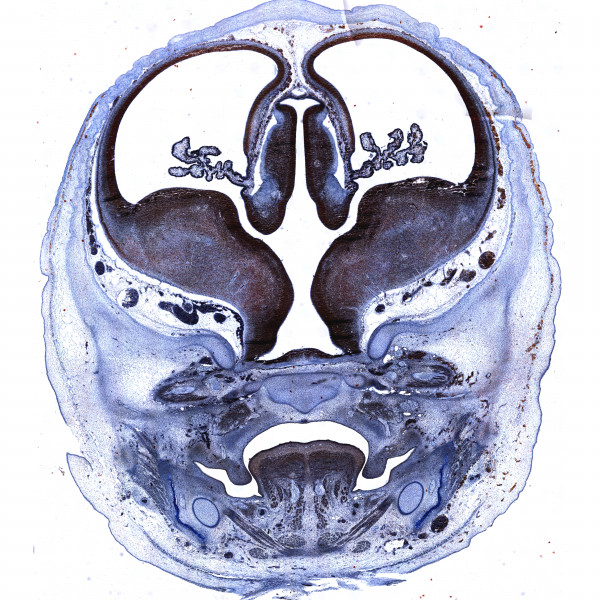

Human brain development atlas

10th gw

Mallory